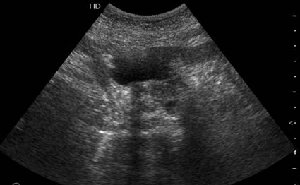

Коллеги, восхищен вашими ответами. Уже много лет работаю в хирургической клинике, но проблема диагностики рака панкреас, дифференциальной диагностики с псевдотуморозным панкреатитом для меня остается актуальной. Ведь очень часто мы даже не видим опухоль даже на неплохом по качеству ультразвуковом оборудовании. Что может помочь в диагнозе?

Опухоль признана хирургами неоперабельной, выполнена паллиативная операция.

Дело в размере и в клинике, и это взаимосвязано. Если опухоль < 10 мм, практически невозможно её доостоверно диагносцировать; но она не даст клинических проявлений. Когда опухоль > 10 мм, она становится хорошо визуализируемой.

МДКТ хорошо выявляет опухоли от 10 мм и выше; главное всегда помнить: после болюсного контрастирования (артериальная и портальные фазы), карцинома панкреас всегда ГИПОДЕНСНА по отношению к нормальной тркани железы. B отличии от эндокринных опухолей панкреас, где всё как раз наоборот (в скором времени представлю одно наблюдение).

МРТ стоит где-то рядом с МДКТ, лучше показывает стадию и степень инвазии, плюс МРХПГ для "красивой" оценки желчных путей.

В умных журналах обсуждают применение УЗИ при эндоскопическом обследовании (endoscopic US), некоторые даже предлагают рутинно использовать для оценки головки панкреас при гастродуоденоскопии. Но это пока весьма дискутабельно.